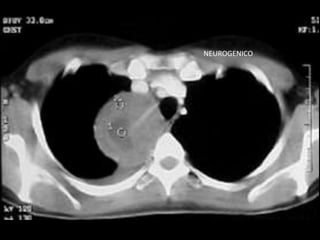

NEUROGENICO

NEUROGENICOS

• Ubicación: mediastino posterior

• Edad: sin predominio

• Clínica: dolor, síndrome medular

• Diagnóstico:

– RMN para ver invasión de canal raquídeo

• Tratamiento: cirugía

NEUROGENICOS • Ubicación: mediastinoposterior • Edad: sin predominio • Clínica: dolor, síndrome medular • Diagnóstico: – RMN para ver invasión de canal raquídeo • Tratamiento: cirugía